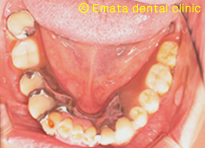

Before

合わない入れ歯

顎の骨の形態から入れ歯はむずかしそうですね。